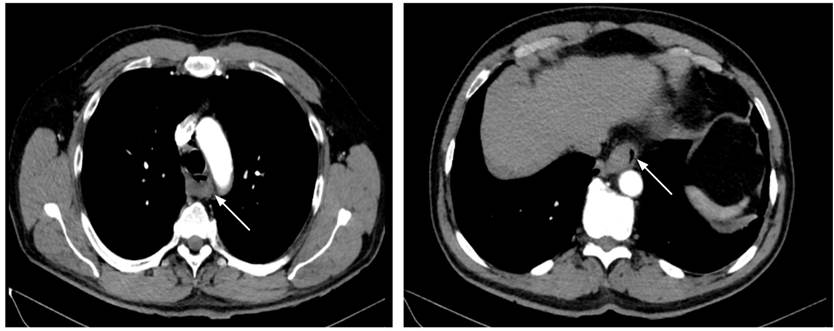

Posteriormente, por la localización e intensidad del dolor se sospechó de una posible disección aórtica, para lo que se realiza una angio-TAC (tomografía axial computarizada) de tórax, que resulta negativa para alteraciones vasculares (Figura 1).

Figura 1 Angio-TAC de tórax: la flecha blanca señala un hematoma a nivel del esófago.